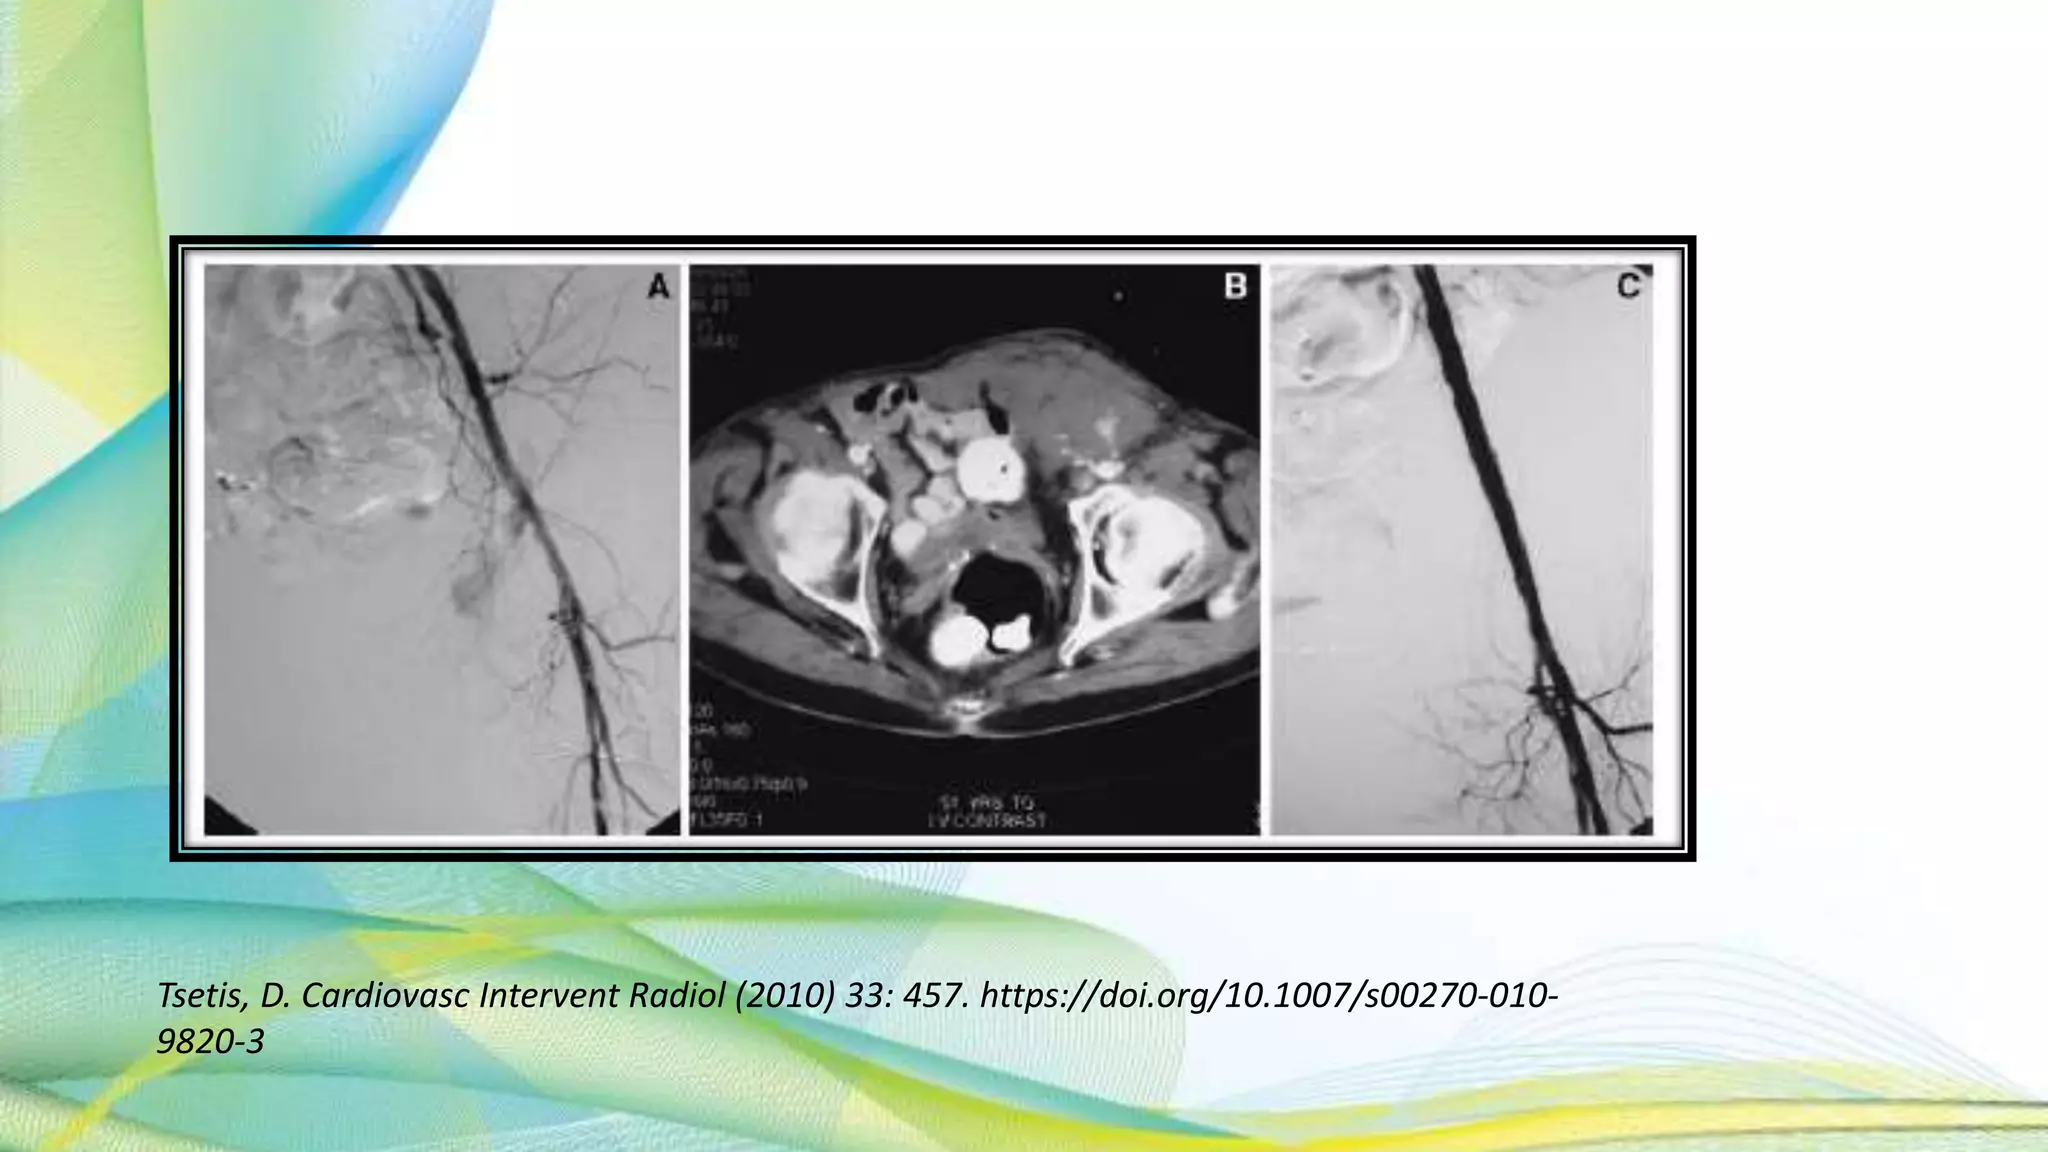

COMPLICATIONS

HEMATOMA

• Signs – hypotension , tachycardia , loss of I/L distal pulse , faintness ,

confusion , agitation and abd pain

• Abdominal CT – to look for hematoma

• Mark the hematoma with pen for change in size assessment

• Endovascular procedure : stent-graft placement (>1mm diameter of

vessel for adequate anchorage )

• Completion angiogram to confirm the success

• Surgical evacuation If massive

Tsetis, D. Cardiovasc Intervent Radiol (2010) 33: 457. https://doi.org/10.1007/s00270-010-9820-3